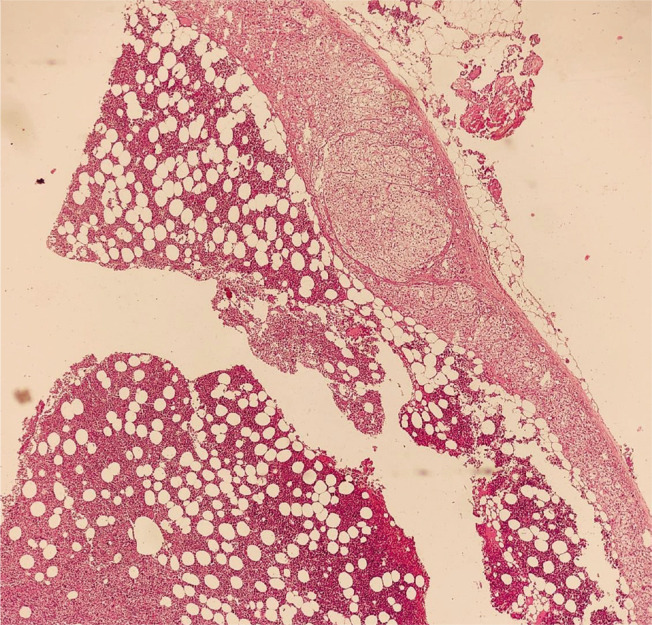

肾上腺髓磷脂瘤(AML)是一种罕见的良性、无症状、无功能的肾上腺皮质肿瘤。AML可同时伴有其他几种内分泌紊乱。在此,我们报告一例36岁女性原发性甲状腺功能减退和代谢综合征,并伴有严重高血压和嗜铬细胞瘤。然而,切除肾上腺的组织病理学检查证实为骨髓脂肪瘤。手术后,她的血浆去甲肾上腺素水平降至正常值,患者血压正常,这表明肿块功能正常。

Adrenal myelolipoma (AML) is a rare, benign, asymptomatic, nonfunctioning tumor of the adrenal cortex detected incidentally. AML can be accompanied by several other endocrine disorders simultaneously. Here, we report a case of a 36-year-old female with primary hypothyroidism and metabolic syndrome accompanied by severe hypertension and pheochromocytoma. However, the histopathological examination of the excised adrenal gland confirmed myelolipoma. Following surgery, her plasma nor-metanephrine levels decreased to normal values and the patient became normotensive, which suggested that the mass was functioning.